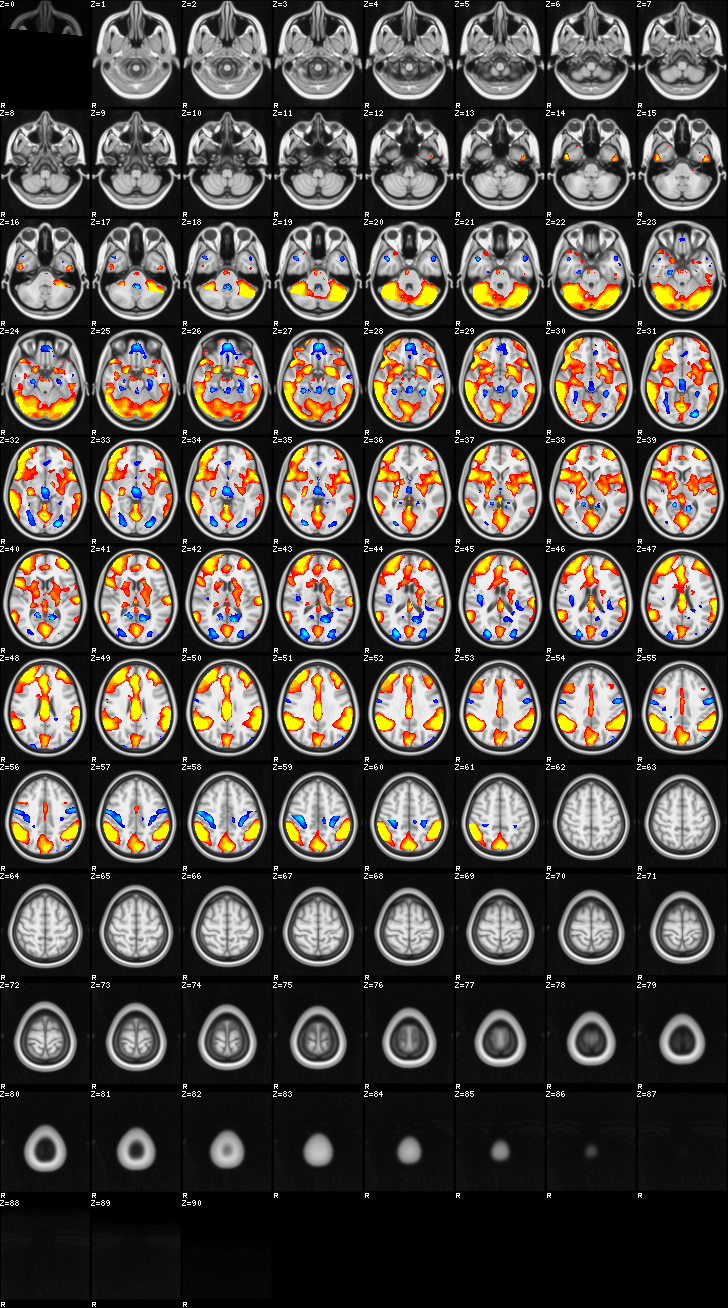

Mixed Effect (flame1)¶

ATM it is 26 subjects, 8 mm FWHM spatial (simple gaussian) smoothing, preliminary results only

Images thresholded abs value > 2.3 and colormap goes from 2.3 to 5 (red->yellow) or -2.3 to -5 (blue->lightblue)

02-MOTOR¶